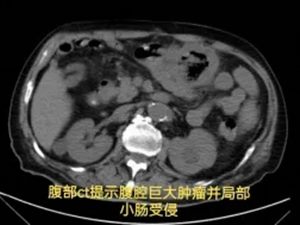

胃肠·甲状腺外科罗昭锋副主任医师会诊后,结合患者手术史与影像学检查,作出关键判断:结肠肿瘤复发并活动性出血——此时,可能只有外科手术才能扭转乾坤。

经积极输血、肠镜证实诊断后,患者转入胃肠·甲状腺外科接受手术治疗。术中探查到如同"炸弹"一样的巨大肿瘤。经仔细"拆弹",团队完整切除了出血部位的复发肿瘤,以及被侵犯的3处小肠。